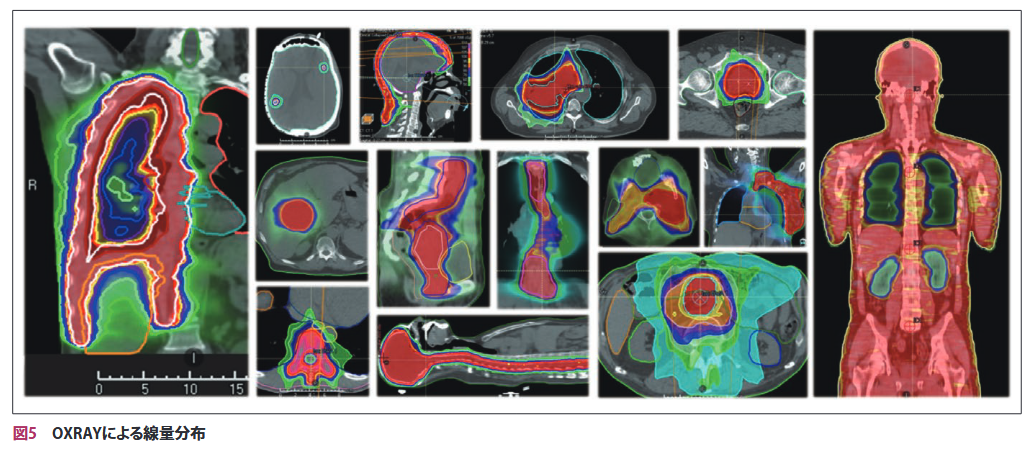

また、図3で示した照射可能範囲を拡大させたプランとの併用や、DSA軌道のカスタマイズ、マルチアイソセンタ照射技法などを活用することにより、OXRAYの最大照射野サイズである20cmを超える標的にも対応できる(図5)。